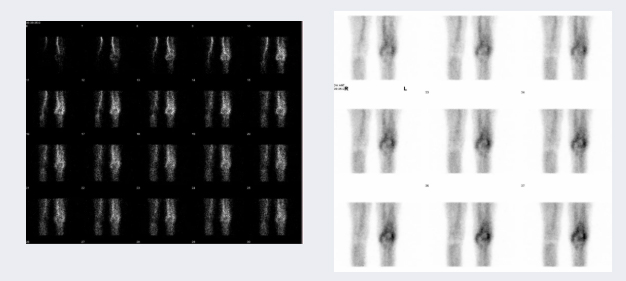

骨动态显像

▲左为早期血流像,右为血池像

▲延时全身骨显像

能获得局部骨和周围组织的“血流相”、“血池相”、“延时相”,能反映局部血流灌注和通畅情况,也能反映软组织的血流分布情况,能更准确地早期鉴别骨髓炎和蜂窝组织炎、股骨头缺血坏死、人工关节的松动与感染、也有助于骨病良恶性的鉴别等。